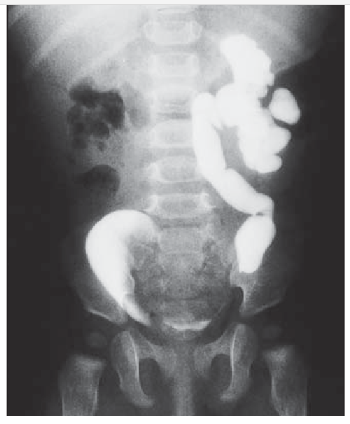

- Fase Pielográfica (Excretora - 5, 10, 15 min): Opacifica o sistema coletor (cálices, pelve, ureteres). Imagens com compressão abdominal podem ser usadas para melhor distensão dos cálices.

- Fase Cistográfica (Bexiga - ~20-30 min): Avalia a bexiga cheia.

- Contornos Renais: Lisos, com tamanho de 3-4 vértebras.

- Nefrograma: Simétrico e homogêneo.

- Pielograma: Cálices côncavos e afilados. Ureteres finos com peristalse visível.

- Cistograma: Bexiga com contornos regulares.